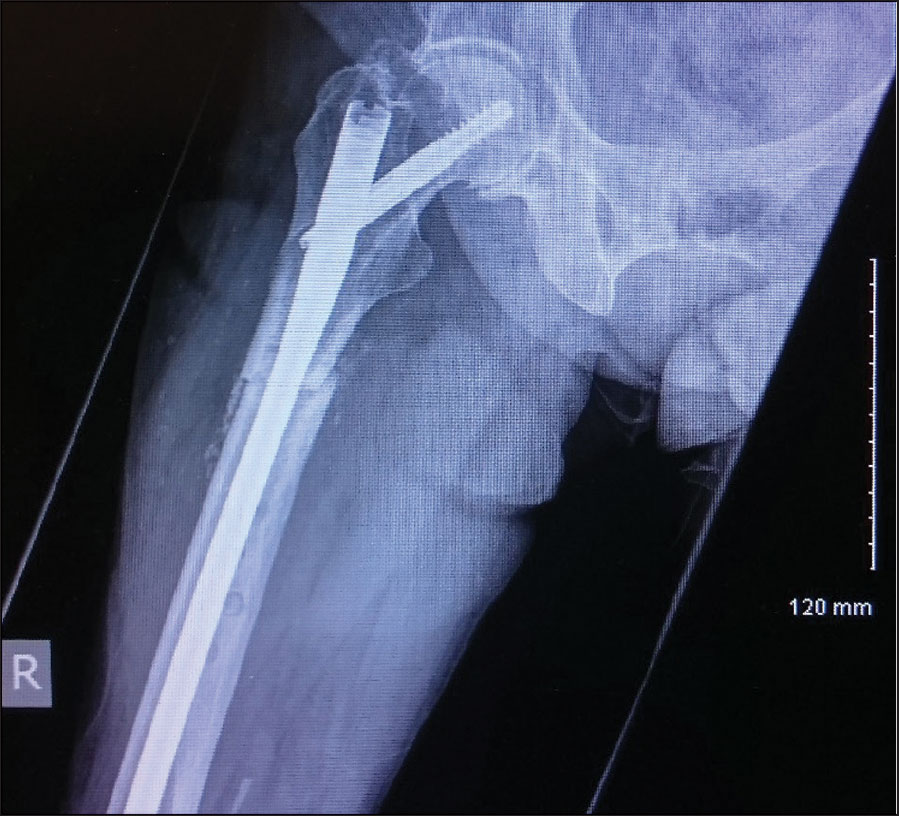

She had an x-ray right femur and pelvis showing an atypical right femur sub-trochanteric fracture. She was taken to the theatre the next day and her two-hole plate was removed without taking the lag screw and was replaced with an eight-hole DHS plate. She was started on physiotherapy and within a few weeks she was walking with a walking frame. She was followed up with regular x-ray. Her alendronate was stopped and she started on teriparatide injections. Teriparatide is a man-made form of the hormone parathyroid which exists naturally in the body.

She was undergoing this treatment when in April 2015 she again had a low energy fall and was brought to hospital with pain right thigh and non-weight bearing. On x-ray she had DHS implant failure. She had the non-union of the original sub trochanteric fracture.

She was taken to theatre again and the DHS implant was removed. A long cephalomedullary nail was inserted. After that she was again started on physiotherapy.